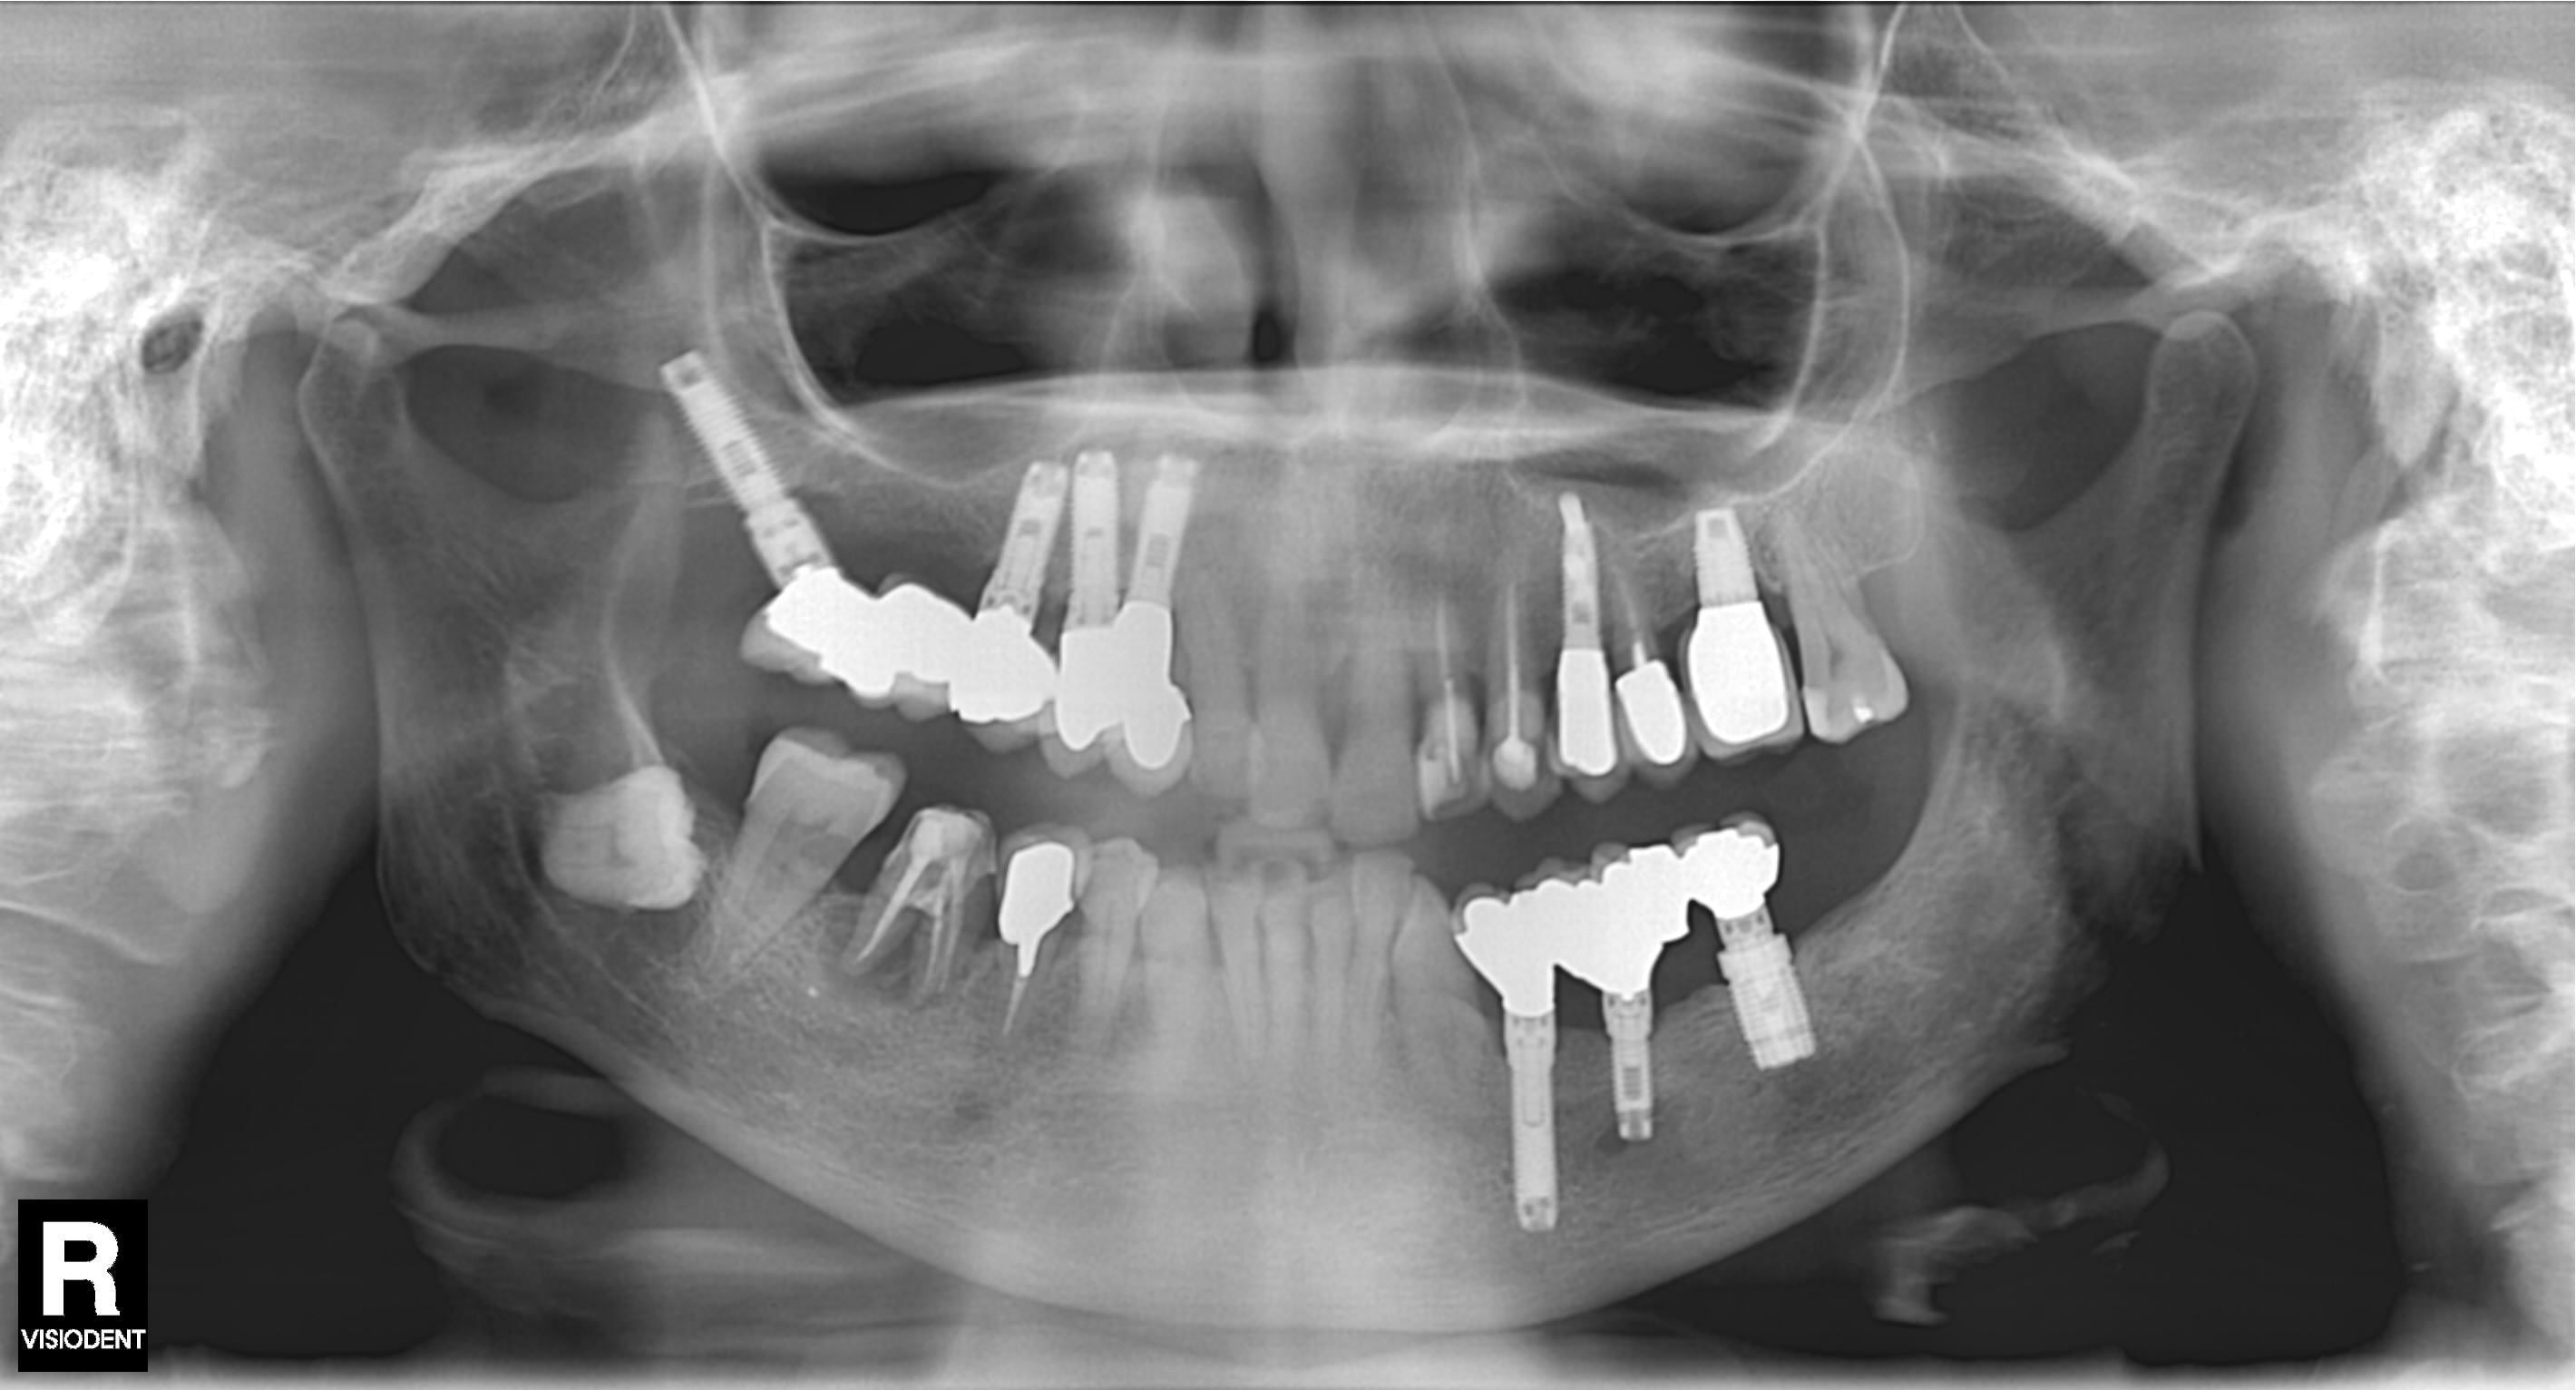

quelqu'un a-t-il une idée de la marque de ses implants secteur 1

forte chances que çà soit du Nobel branemark mk1

C’est une patiente de 92 ans qui est venue avec son bridge dévissé je n’ai pas voulu l’embêter j’ai envoyé la pano que j’avais depuis un moment